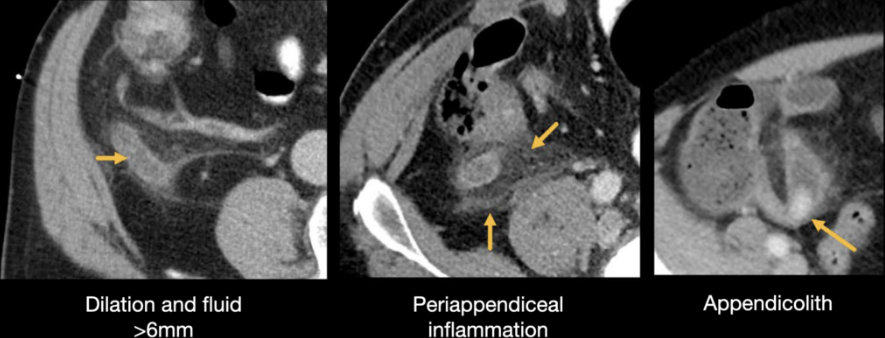

CT Imaging: Normal vs. abnormal

Imaging

• CT with IV contrast: Sensitivity and specificity both >95%

• Preferred in adults

• Dilated appendix >6 mm, peri-appendiceal fat stranding

• Ultrasonography: First-line in children and pregnant women

• Sensitivity 70–90%

• MRI: Alternative in pregnancy